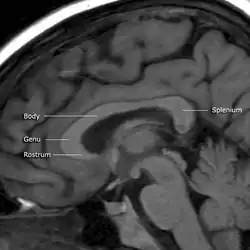

![]() Sagittal section of a brain, front part to the left. The corpus callosum can be seen in the center, in light gray | |

The corpus callosum (Latin for "tough body"), also callosal commissure, is a wide, thick nerve tract, consisting of a flat bundle of commissural fibers, beneath the cerebral cortex in the brain. The corpus callosum is only found in placental mammals.[1] It spans part of the longitudinal fissure, connecting the left and right cerebral hemispheres, enabling communication between them. It is the largest white matter structure in the human brain, about 10 cm (3.9 in) in length and consisting of 200–300 million axonal projections.[2][3]

A number of separate nerve tracts, classed as subregions of the corpus callosum, connect different parts of the hemispheres. The main ones are known as the genu, the rostrum, the trunk or body, and the splenium.[4]

The corpus callosum forms the floor of the longitudinal fissure that separates the two cerebral hemispheres. Part of the corpus callosum forms the roof of the lateral ventricles.[5]

The corpus callosum has four main parts – individual nerve tracts that connect different parts of the hemispheres. These are the rostrum, the genu, the trunk or body, and the splenium.[4] Fibres from the trunk and the splenium, known together as the tapetum ("carpet"), form the roof of each lateral ventricle.[6]

The front part of the corpus callosum, towards the frontal lobes, is called the genu ("knee"). The genu curves downward and backward in front of the septum pellucidum, diminishing greatly in thickness. The lower, much thinner part is the rostrum and is connected below with the lamina terminalis, which stretches from the interventricular foramina to the recess at the base of the optic stalk. The rostrum is named for its resemblance to a bird's beak.

The end part of the corpus callosum, towards the cerebellum, is called the splenium. This is the thickest part, and overlaps the tela choroidea of the third ventricle and the midbrain, and ends in a thick, convex, free border. Splenium translates as "bandage" in Greek.

The trunk of the corpus callosum lies between the splenium and the genu.